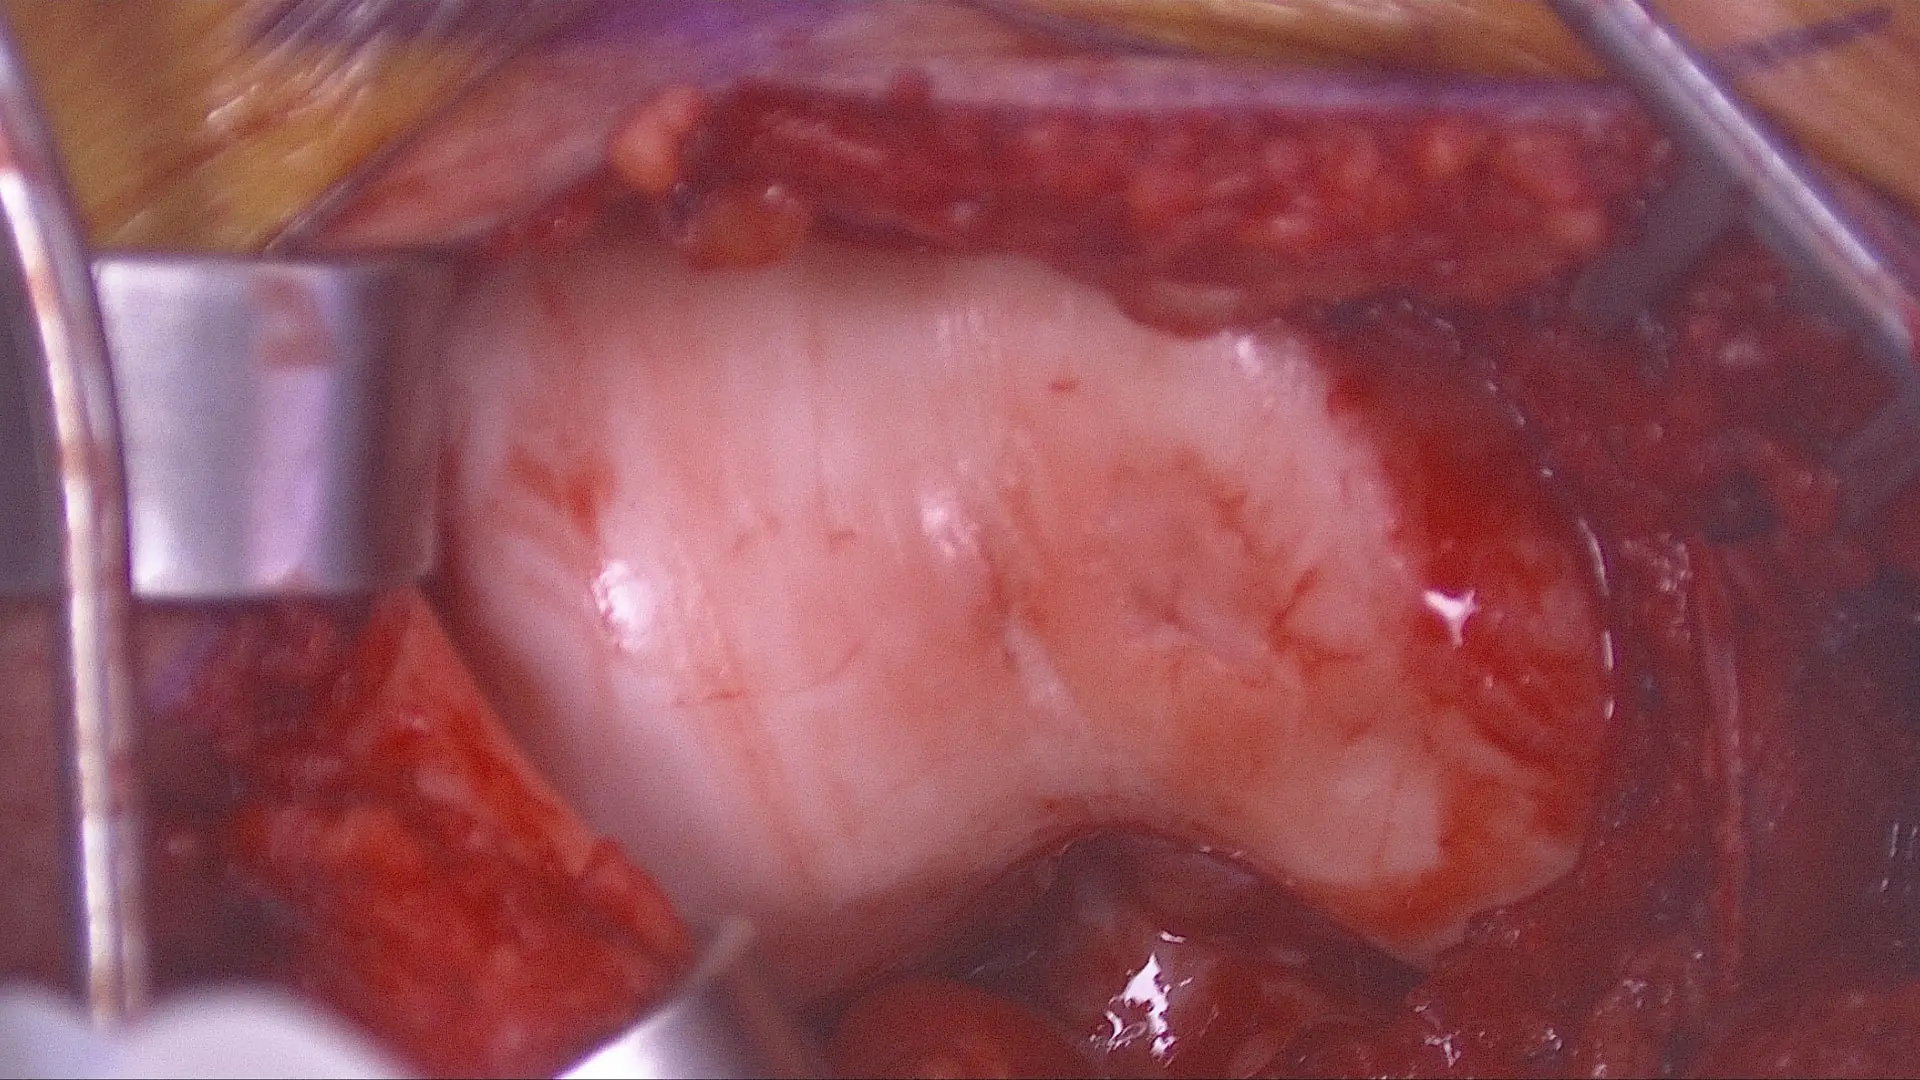

The actual BEAR Implant “looks like a large marshmallow that is soaked with the patient’s own blood. It works as a scaffold that helps bridge the gap between the torn ends of the ACL,” he explains.

A surgeon prepares a BEAR Implant prior to surgery.